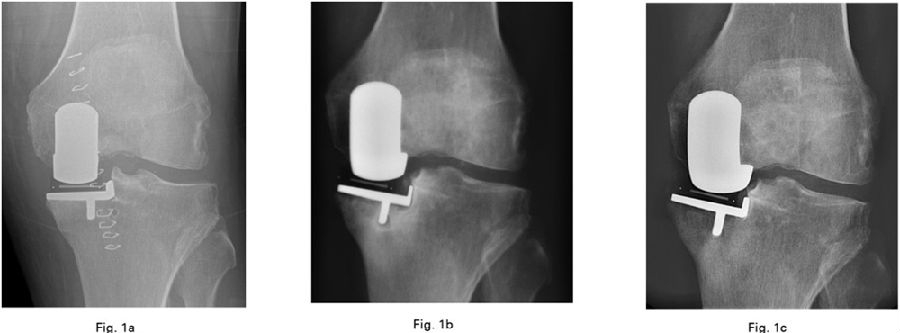

A内外侧位置把握较好,B过于靠内,C过于靠外

假体组件的位置:内外侧